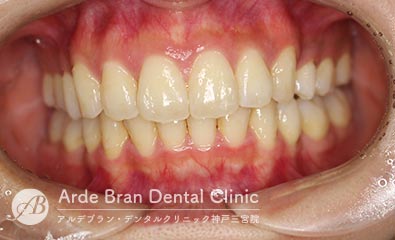

- 叢生/過蓋咬合/シザースバイト(20代女性 治療期間1年5カ月)

- 歯のがたつきと突出感を改善したいとの事でご来院されました。当院で精査した所、奥歯の前後的な位置関係にもズレがあり、前歯のかみ合わせも深く、また左側の奥歯も一部かみ合っていない場所がありました。顎間ゴムを用いて奥歯の前後的な位置関係を改善し、かみ合わせも整えました。なるべく目立たない装置で、可能であれば歯を抜きたくないとの事だったのでインビザラインフルにて治療を行いました。

- 治療前

- 治療後

| 装置名 | インビザライン(マウスピース矯正) |

| 抜歯非抜歯 | 非抜歯 |

| 治療期間 | 1年5カ月 |

| 費用 | インビザラインフル72万円+TAX 再印象(5千円+TAX)×1回 顎間ゴム500円×数個 |